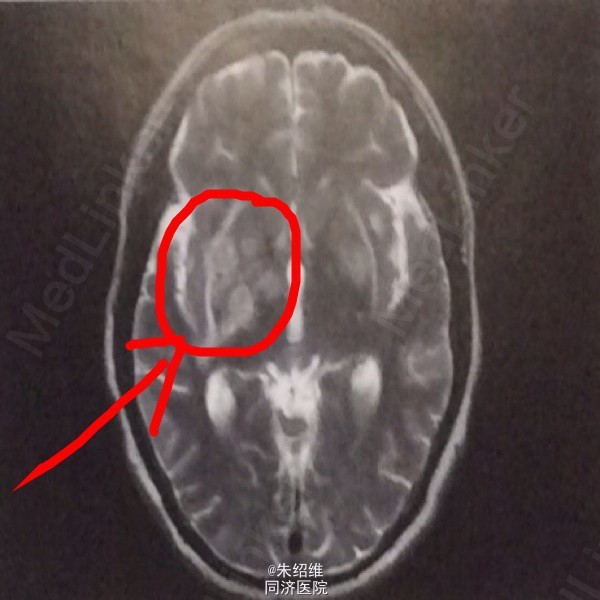

体检:脑膜刺激症阳性。MRI示两侧基底节区多发斑片状T1低信号,T2高信号,边界模糊,灶周水肿。增强病灶斑点状轻度强化。

诊断:双侧基底节区新型隐球菌脑病。给予抗真菌,降颅压治疗。